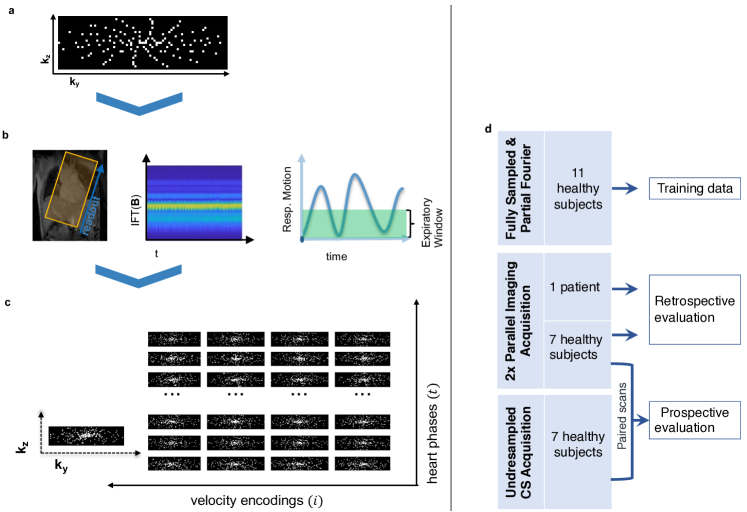

As illustrated in Fig. 1a, for each velocity encoding direction, the k-space data is acquired using a Cartesian Golden angle sampling strategy, yielding variable density undersampling patterns in k-space. The signal of a total of 28 physical coils is compressed into 5 virtual coils via clustering 25. The samples are then sorted into respiratory bins and data in the end-expiratory bin is used for reconstruction.

In Vivo Data Acquisition

As illustrated in Fig. 1, we used 11 subject for network training, and 7 healthy subjects and 1 patient for evaluation. All in-vivo work was performed upon written informed consent of the subjects and according to local ethics regulations.

Training datasets comprised 4D flow data measured in the aorta of 11 healthy subjects, 9 of them fully sampled and 2 acquired with partial Fourier 38 (factor 0.750.75).

For evaluation, data in the ascending aorta of 7 healthy subjects were acquired on a 3T Philips Ingenia system (Philips Healthcare, Best, the Netherlands) using a Cartesian 4-point referenced phase-contrast gradient-echo sequence with an encoding velocity , a spatial resolution of , , , cardiac phases and flip angle = 8∘. Exams for each of the 7 healthy subjects comprised a standard navigator-gated 2-fold accelerated parallel imaging 5 exam for reference, and a CS acquisition with an acceleration factor of =, using Cartesian pseudo-radial golden angle sampling pattern 39 and data driven-respiratory motion detection, as in 11. Only data in expiration were kept for reconstruction as shown in Fig. 1.

To evaluate reconstruction accuracy on pathological anatomy, 4D flow data was acquired in a single patient with dilation of the ascending aorta, combined aortic stenosis and regurgitation due to a bicuspid aortic valve on a 3T Philips Ingenia system (Philips Healthcare, Best, the Netherlands) using a navigator-gated 2-fold accelerated parallel imaging 5 scan.